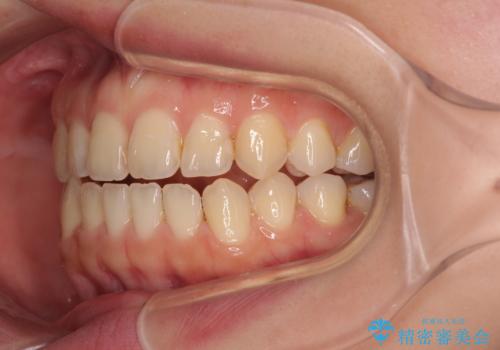

前歯のオープンバイト インビザラインで咬み合わせを改善

- 前歯の開咬を気にして来院された患者様です。

開咬の治療は、前歯を閉じるように動かすとともに、上下臼歯を圧下(骨内にめり込ませる)させることで進めて行きます。

インビザラインは臼歯の圧下を効果的に行えるため、インビザラインを用いて矯正治療を行うこととしました。